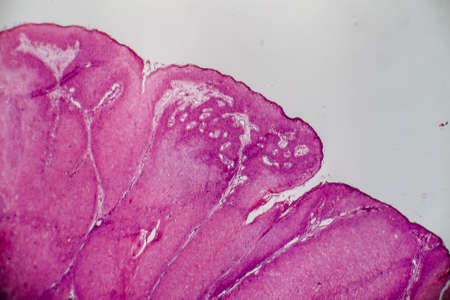

Pathology and Histology Tissue of Mammals under microscope.

Education anatomy and Histological sample of Human under the microscope.